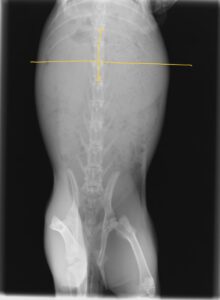

実際の症例

半日前から食欲低下、うんちが出なくなって来院したうさぎです。

レントゲンを撮ると、黄色線が最後肋骨であり、本来はここまでに胃のサイズが収まってほしいのですが、それを大きく出ています。

そして、入院し、治療した翌日のレントゲンが下です。

胃のサイズが小さくなっているのがわかると思います。

このまま退院し、通院にて数週間で完治しました。